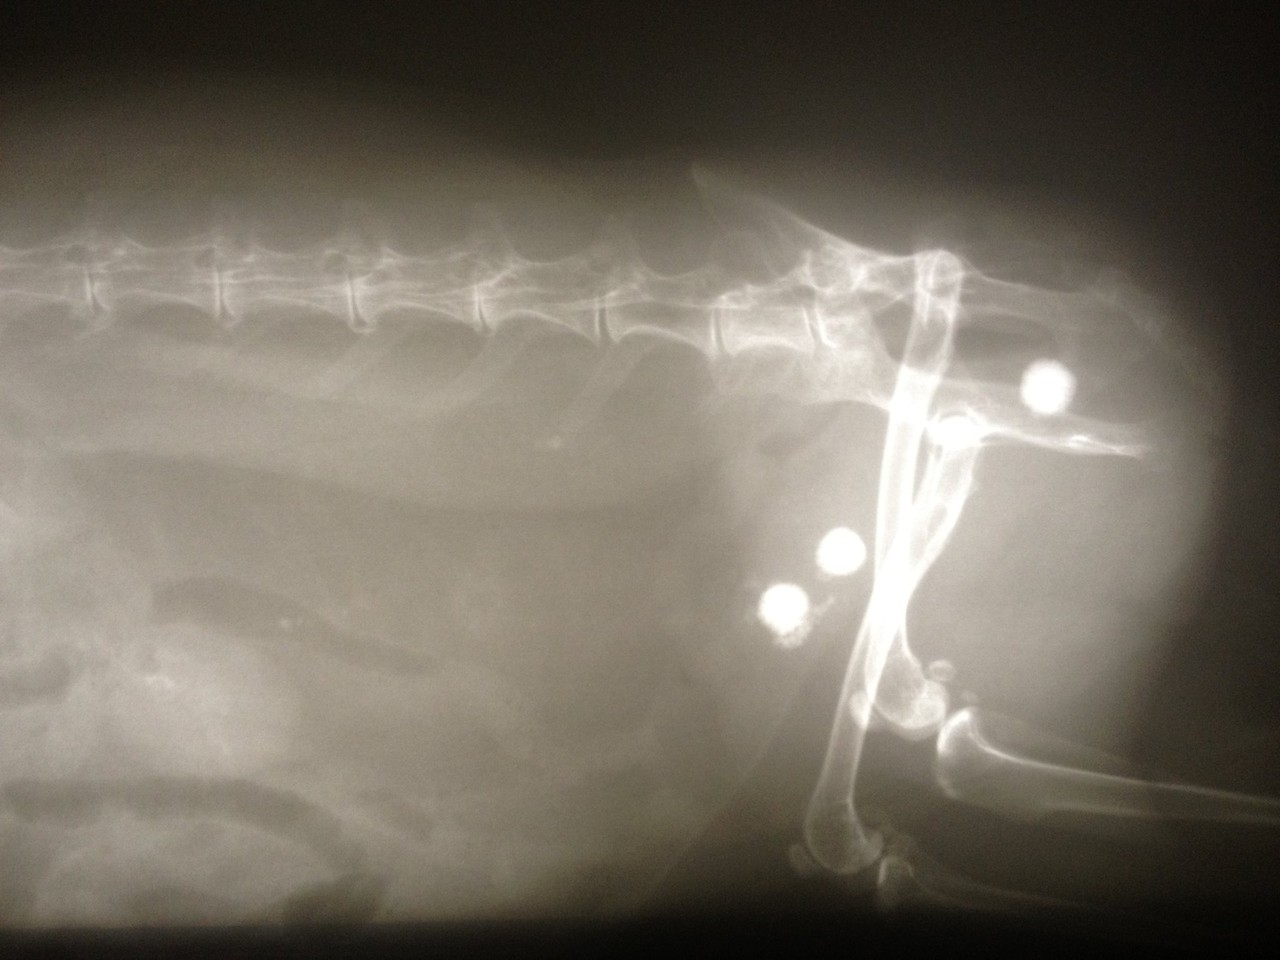

Schwer zu sagen alleine anhand des Bildes Ist die Operationswunde noch verschlossen?. Antikörpernachweis im Blut (Bestimmung des Titers) Antikörpernachweis im Urin (Bestimmung des Titers nur nachweisbar, wenn die Nieren befallen sind) Durch eine Antikörperbestimmung wird nachgewiesen, ob ein Tier infiziert ist Über den Schweregrad der Erkrankung lässt sich keine Aussage treffen. Die Einstreu im Kaninchenkäfig muss trocken gehalten werden, um eine Dermatitis der Harnwege zu vermeiden Bei schwerwiegenderen Symptomen im Zusammenhang mit dem Vorhandensein von Blut im Urin sollten Sie sich an den Veterinärdienst wenden.

Meine Frau hat zwei Kanninchen Eines davon hat nach der Kastration Urin im Blut Der Tierarzt meint, dass es nichts mit der OP zu tun hat, es müsste eine Blasenentzündung sein Doch nach 10 en Medizin gibt es keine Besserung. Da die Erreger mit Kot und Urin ausgeschieden werden, können sich gesunde Kaninchen über kontaminierte Einstreu und Futter infizieren Eine Heilung ist nicht möglich Bei frühzeitiger tierärztlicher Behandlung kann die akute Erkrankung jedoch so weit zurückgedrängt werden, dass die Kaninchen symptomfrei leben können. Da die Erreger mit Kot und Urin ausgeschieden werden, können sich gesunde Kaninchen über kontaminierte Einstreu und Futter infizieren Eine Heilung ist nicht möglich Bei frühzeitiger tierärztlicher Behandlung kann die akute Erkrankung jedoch so weit zurückgedrängt werden, dass die Kaninchen symptomfrei leben können.